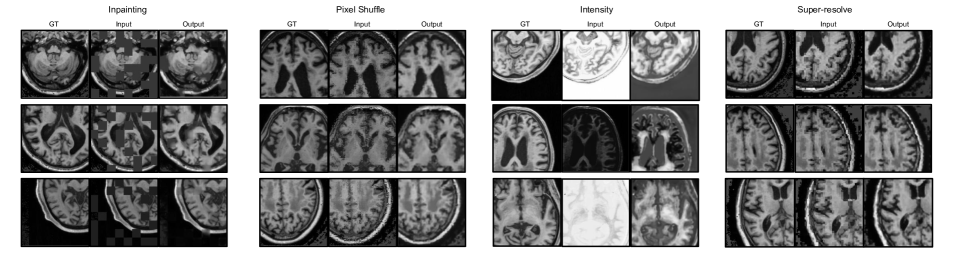

Refer to caption

Fig. 4: Visual examples of baseline self-supervised tasks. The results with best validation performance are used for visualization. Best viewed with zoom.

We compare the proposed method to four widely used self-supervision tasks for dense prediction [40, 47]. The first three tasks focus on the reconstruction and context-based prediction in an image, while the last task focuses on the intensity correction.

4.1 Inpainting

Image inpainting is the process of reconstructing the missing or damaged contents of an image, historically employed for restoring paintings and photographs [7]. Inpainting, as a self-supervision task, proceeds by intentionally masking selected areas within an image and a network must learn to recover the missing content.

4.2 Local Pixel Shuffling

Local pixel shuffling has been known to aid a network in learning about the local information within an image, without compromising the global structures [47]. This task is similar to inpainting but with additional information on the distribution of intensities to inpaint. In this task, synthetic images are generated by randomly shuffling pixels within the selected grid cell, as shown in the following equation:

4.3 Super-resolution

Super-resolution can be implemented as a self-supervision task [46], wherein a network is trained to deblur the low-resolution image. To create the low-resolution images from high-resolution ones for training, we blur the high-resolution images by transforming every grid cell by replacing all its values with that in the center of the grid:

4.4 Non-linear Intensity Shift

The intensity shift mechanism is proposed by [47], where each pixel value in the image is translated monotonically using a Bezier curve (denoted as function B𝐵B) [36]. In medical imaging, since the intensity values in a image usually correspond to the underlying anatomical details, this task can be used to encourage a network to learn useful anatomical features.